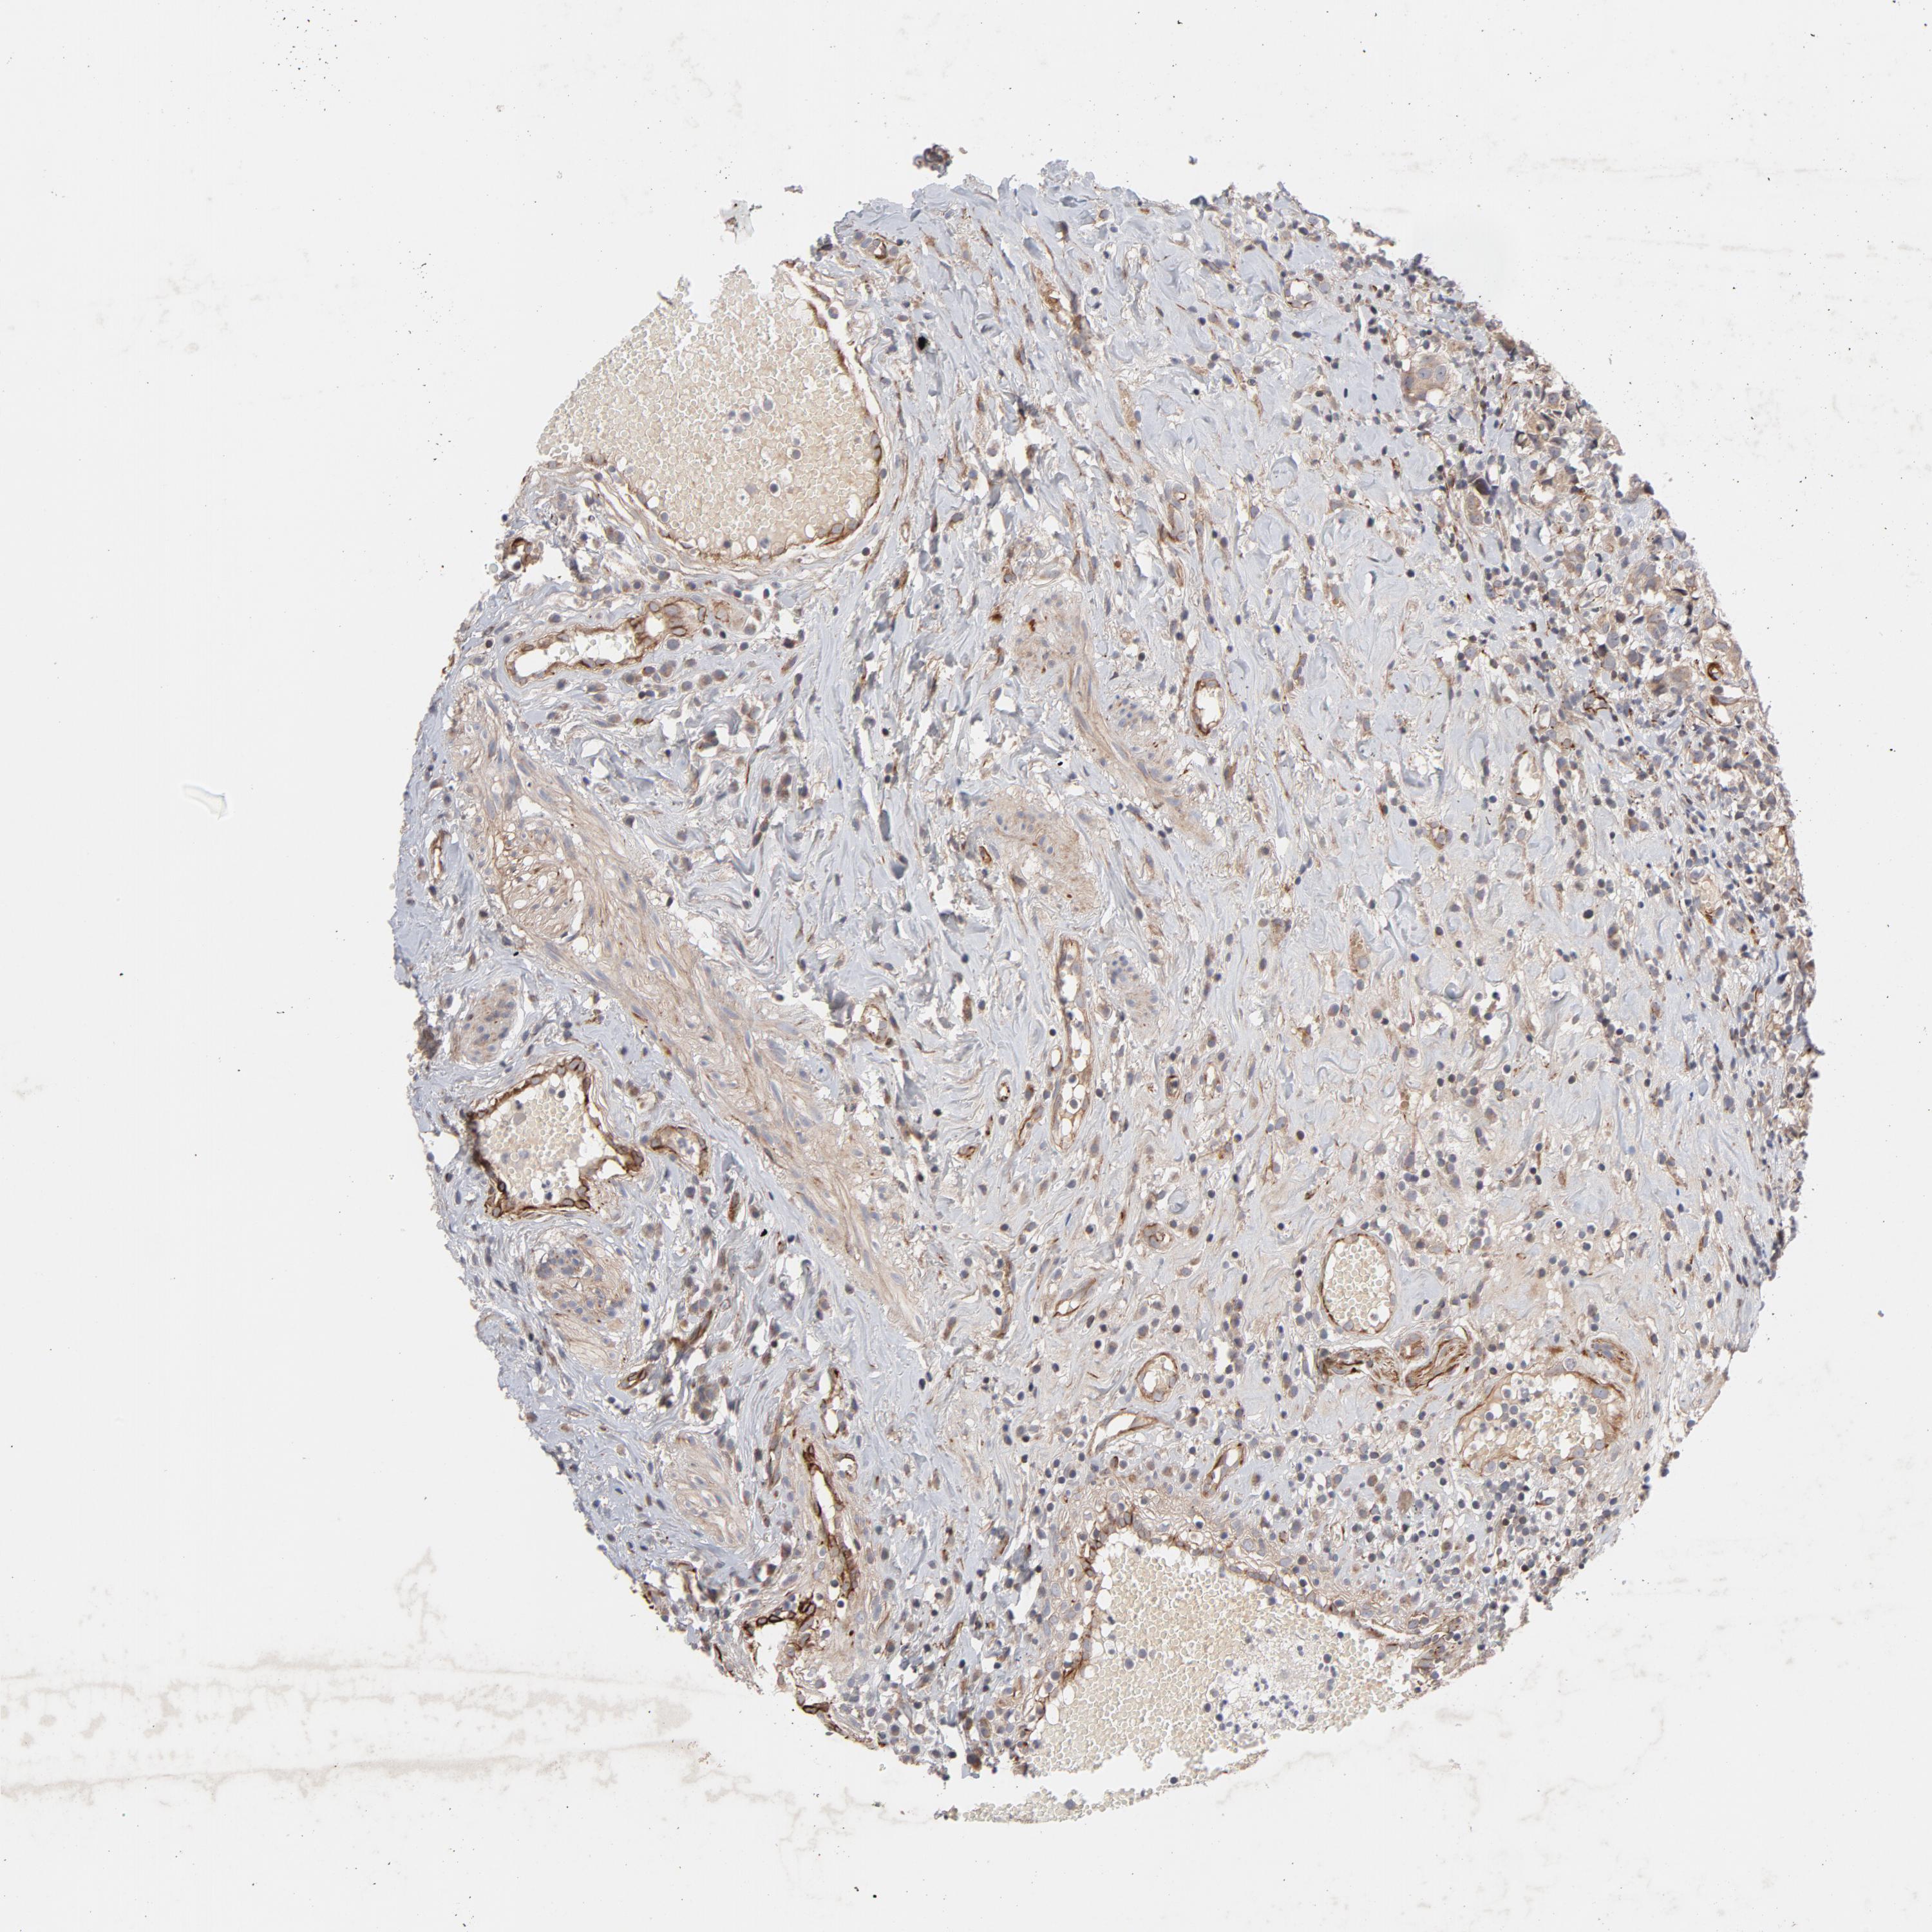

UROTHELIAL CANCER - Protein expressioni

A mouse-over function shows sample information and annotation data. Click on an image to view it in a full screen mode. Samples can be filtered based on level of antibody staining by selecting one or several of the following categories: high, medium, low and not detected. The assay and annotation is described here.

Note that samples used for immunohistochemistry by the Human Protein Atlas do not correspond to samples in the TCGA dataset.

Antibody stainingi

Antibody staining in the annotated cell types in the current human tissue is reported as not detected, low, medium, or high, based on conventional immunohistochemistry profiling in selected tissues. This score is based on the combination of the staining intensity and fraction of stained cells.

Each image is clickable and will lead to virtual microscopy that enables deeper exploration of all samples and also displays staining intensity scores, fraction scores and subcellular localization as well as patient and tissue information for each sample.

Antibody HPA002894

Urothelial carcinoma, High grade